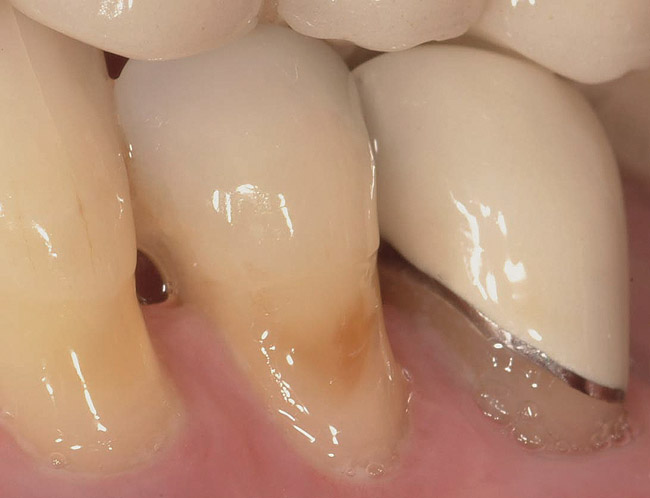

Figure 4  This root surface is black and cavitated. When exploring with the side of the explorer, this root surface will feel soft and sticky, and it may be possible to remove soft debris from this lesion.

Figure 4